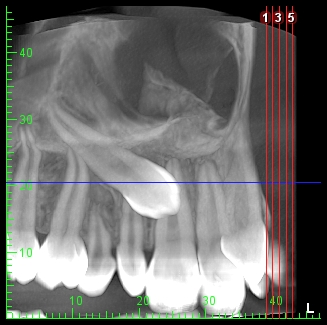

Estudios 3D

- Tomografía volumétrica con técnica de cone beam localizada.

- Tomografía volumétrica con técnica de cone beam para endodoncia. Cortes de 75 Mm

- Tomografía volumétrica con técnica de cone beam Hemiarcada.

- Tomografía volumétrica con técnica de cone beam completa